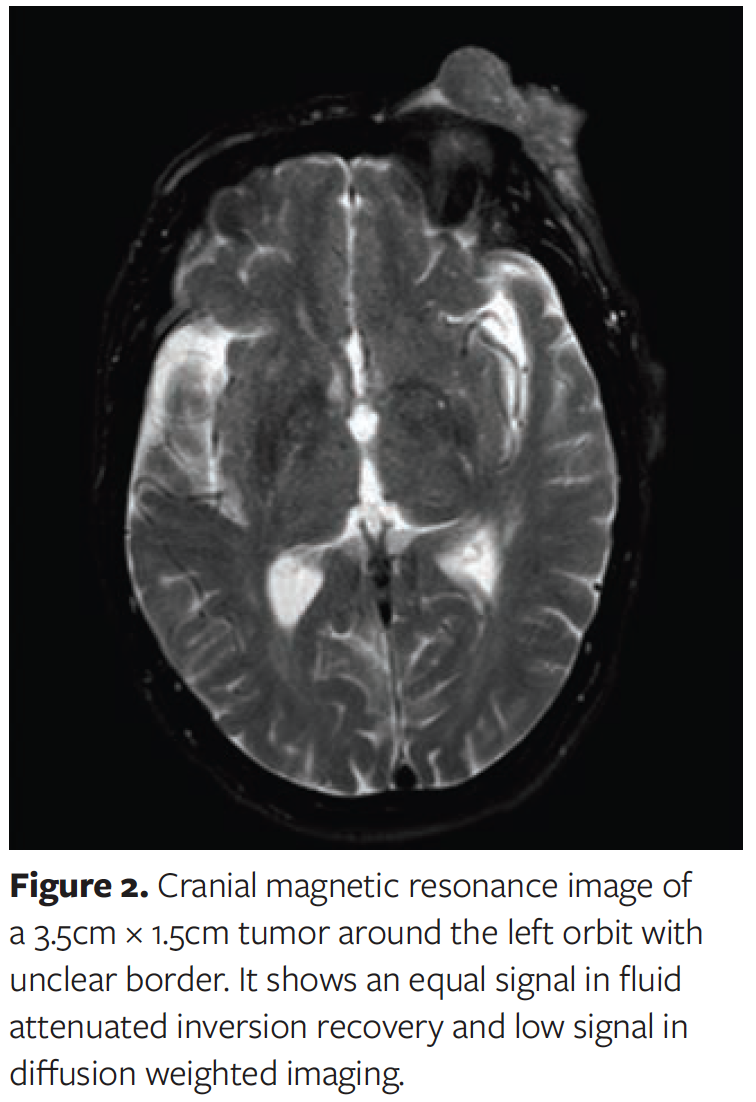

Physical examination revealed a well-demarcated cutaneous tumor measuring 5.2 cm × 3 cm × 2 cm in the left upper eyelid (Figure 1). No enlargement of the superficial lymph nodes was observed. The remaining physical examinations and preoperative laboratory tests were unremarkable. Cranial MRI showed a tumor measuring 3.6 cm × 1.5 cm and equal T1 and short T2 signal. The tumor showed hypointensity on diffusion-weighted imaging and isointensity on fluid-attenuated inversion recovery imaging (Figure 2).